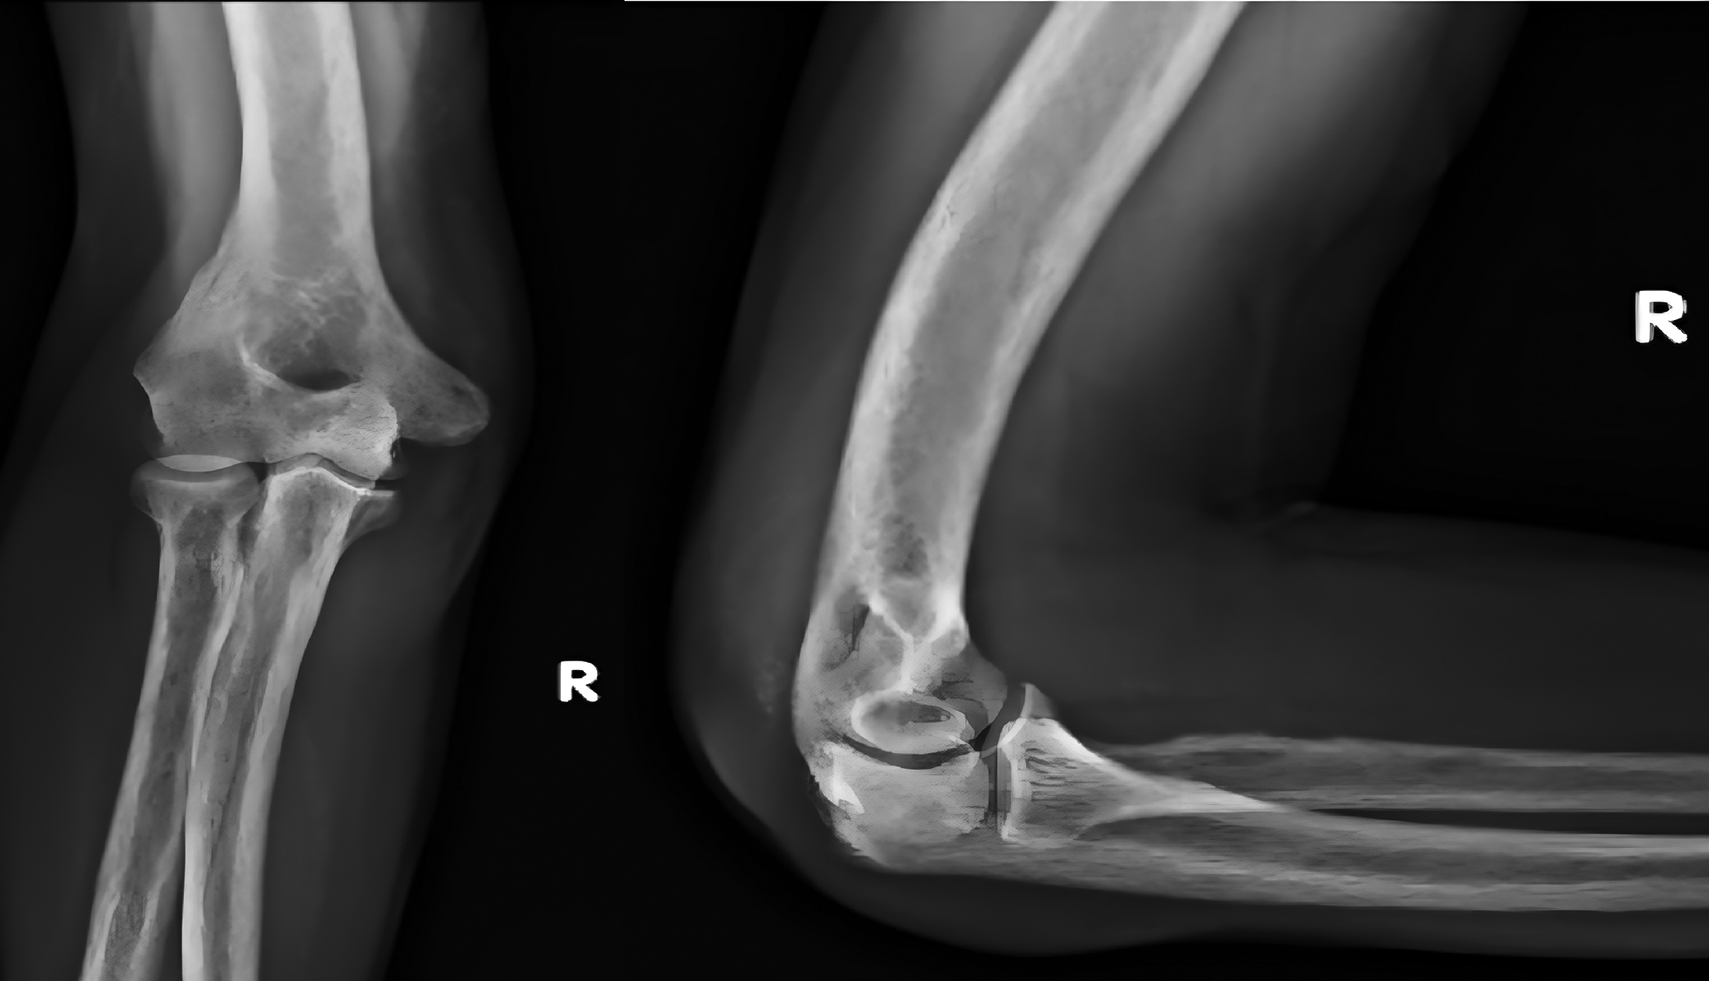

A 44-yr old male with ESRD secondary to immunoglobinA nephropathy with a history of allograft rejection during three weekly hemodialysis sessions for 10 years presented with complaints of right elbow extension weakness following trivial trauma. Physical examination revealed swelling of the right elbow with grade 0 power in the elbow extensor mechanism. Radiographs showed an avulsed triceps tendon (Figure 3).

ba2523aa-b24d-4010-a34b-e26e289433e9_figure3.gif

Figure 3. Anteroposterior and lateral radiographs of Case 2 with avulsed triceps tendon.

He underwent open repair of the triceps tendon with a suture anchor inserted in the olecranon after excision of the devitalized tongue of the tissue (Figure 4). The elbow was immobilized in an above elbow slab at approximately 110° for 6 weeks, after which active mobilization was started. The last follow-up at 7 months revealed grade 5/5 power with full elbow ROM.